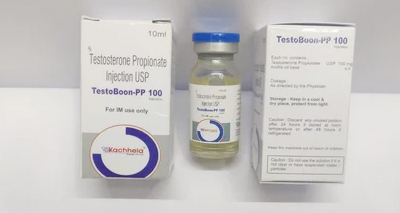

Trending products